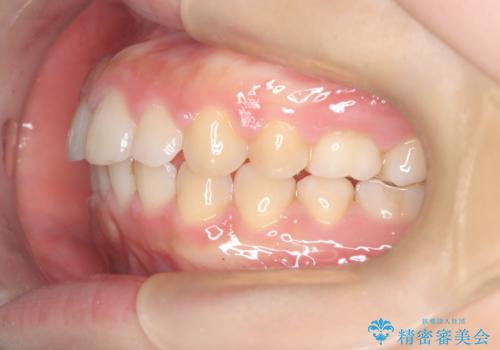

【ワイヤー矯正】前歯のがたがたをなおしたい

- 前歯のがたがたを主訴に来院されました。

叢生量も軽度なため短期間で治療を行っています。

治療中、装置の変更を希望されたため上下で装置が異なっています。